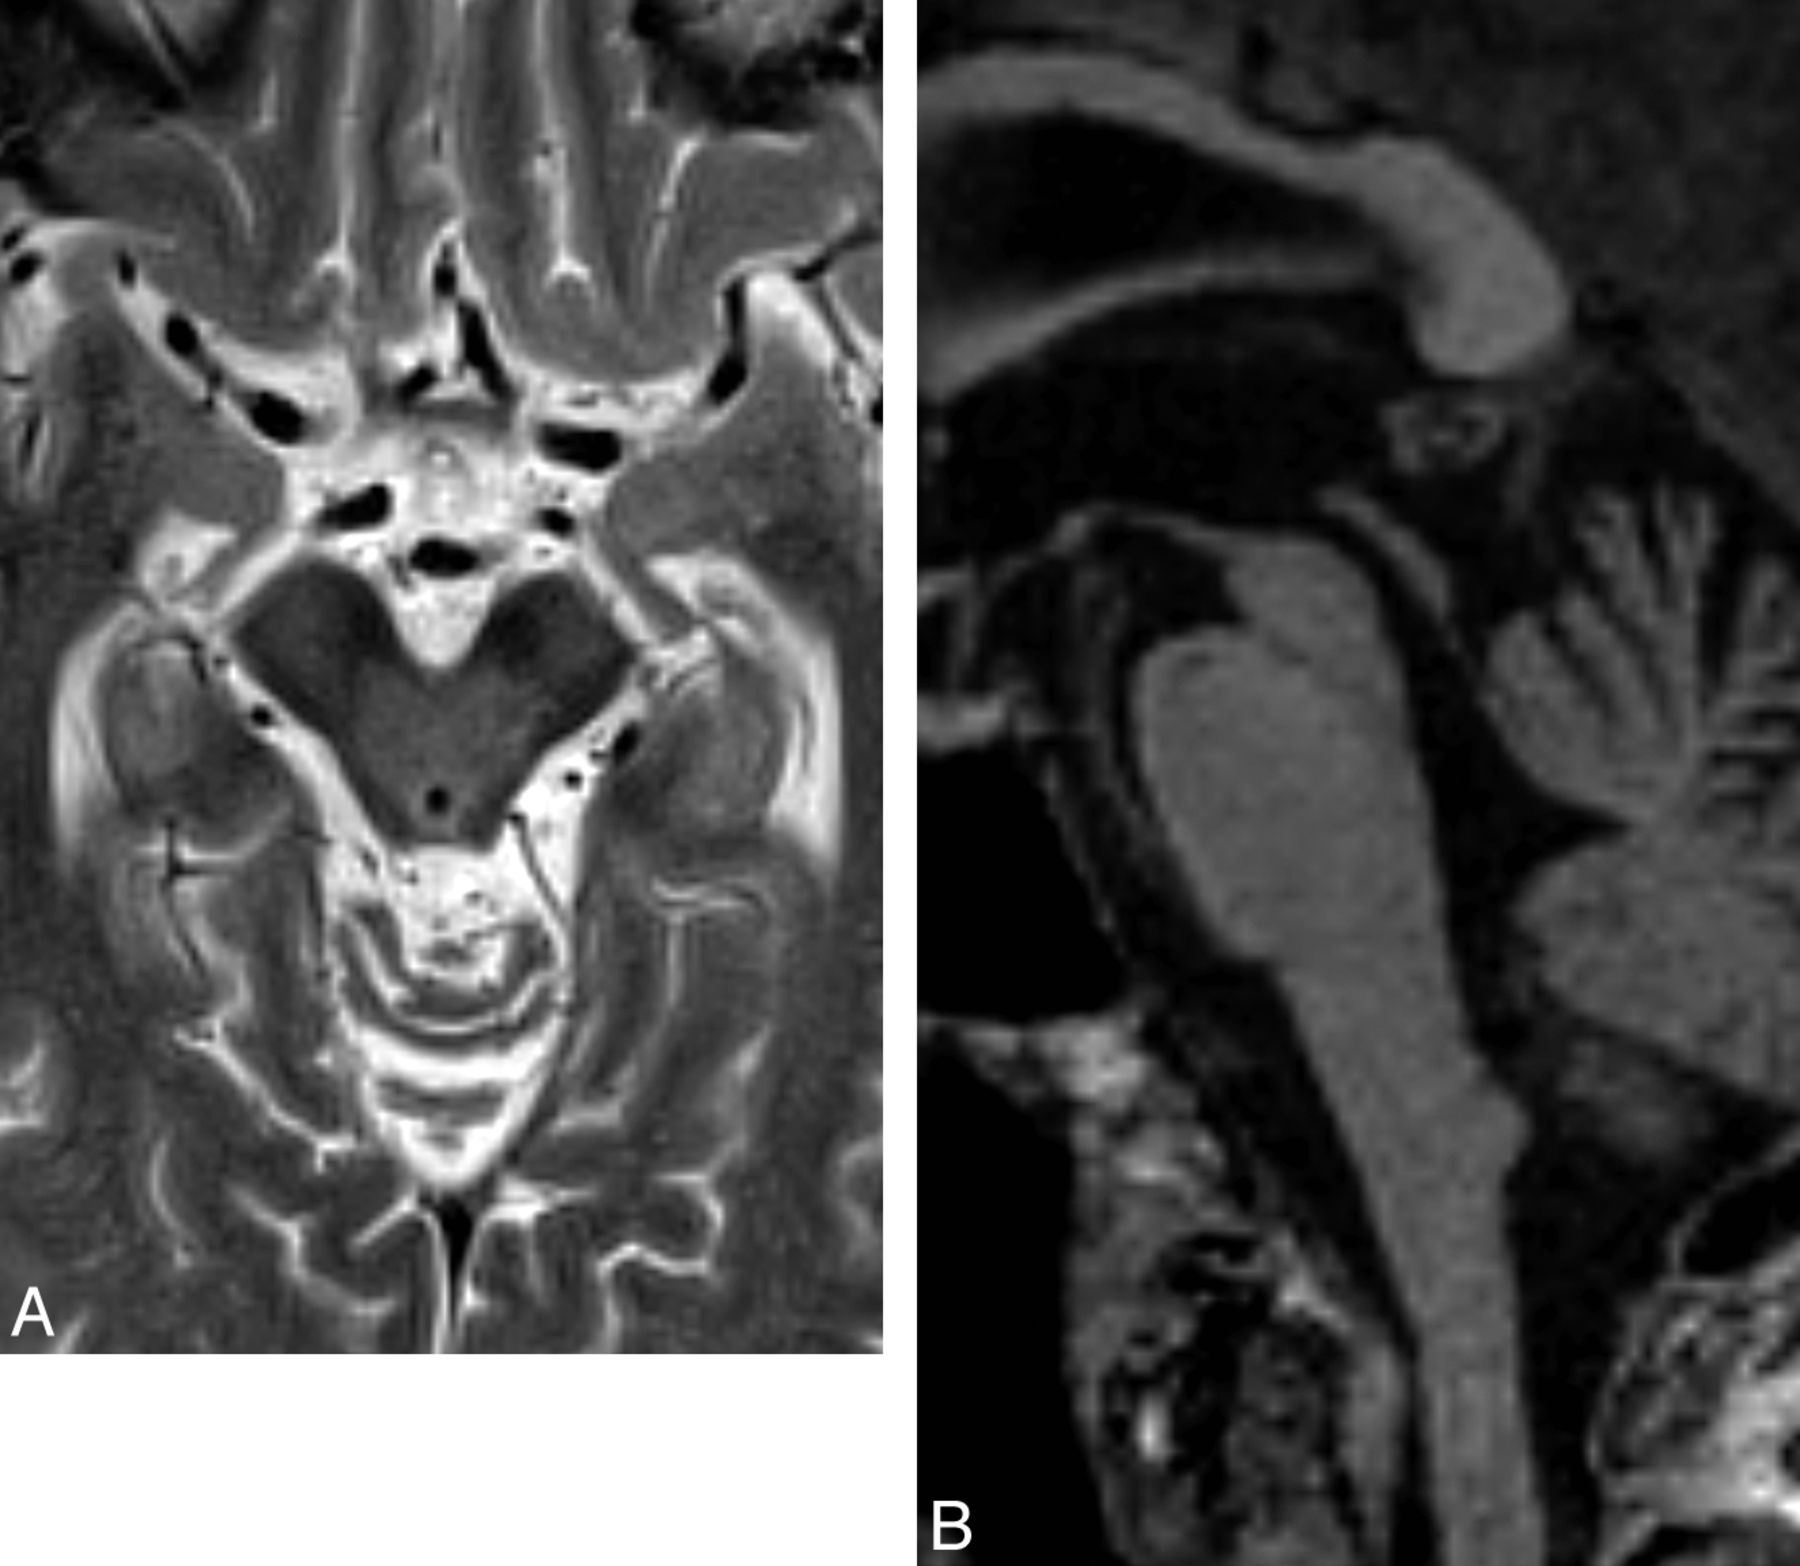

Some studies combining DaT-SPECT with IBZM or IBF have shown that idiopathic Parkinson disease can be differentiated from MSA or PSP,36,37 whereas others have demonstrated otherwise.38,39 More promising is a recent prospective study, which, by using a combination of DaT-SPECT, 123I-IBZM SPECT, and meta-123I-iodobenzylguanidine scintigraphy (which probes myocardial adrenergic denervation seen in idiopathic Parkinson disease), reports a positive predictive value of 89%, and a negative predictive value of 97% (Fig 6).40

Axial 123I-FP-CIT DaT-SPECT, 123I-IBZM, and meta-123I-iodobenzylguanidine SPECT studies in idiopathic Parkinson disease (A) and atypical Parkinson disease (MSA or PSP) (B). Uptake patterns with all 3 radiopharmaceuticals are typical for idiopathic Parkinson disease with asymmetric striatal reduction using 123I-FP-CIT, normal dopamine D2 receptor binding with 123I-IBZM, and reduction in myocardial uptake due to adrenergic denervation with meta-123I-iodobenzylguanidine (A). B, Images demonstrate findings of MSA or PSP: reduced striatal uptake with 123I-FP-CIT and 123I-IBZM but normal myocardial uptake with meta-123I-iodobenzylguanidine. Image courtesy of Dr M. Südmeyer. This was originally published in: Südmeyer M, Antke C, Zizek T, et al. Diagnostic accuracy of combined FP-CIT, IBZM, and MIBG scintigraphy in the differential diagnosis of degenerative parkinsonism: a multidimensional statistical approach. J Nucl Med 2011;52:733–40. © by the Society of Nuclear Medicine and Molecular Imaging, Inc.